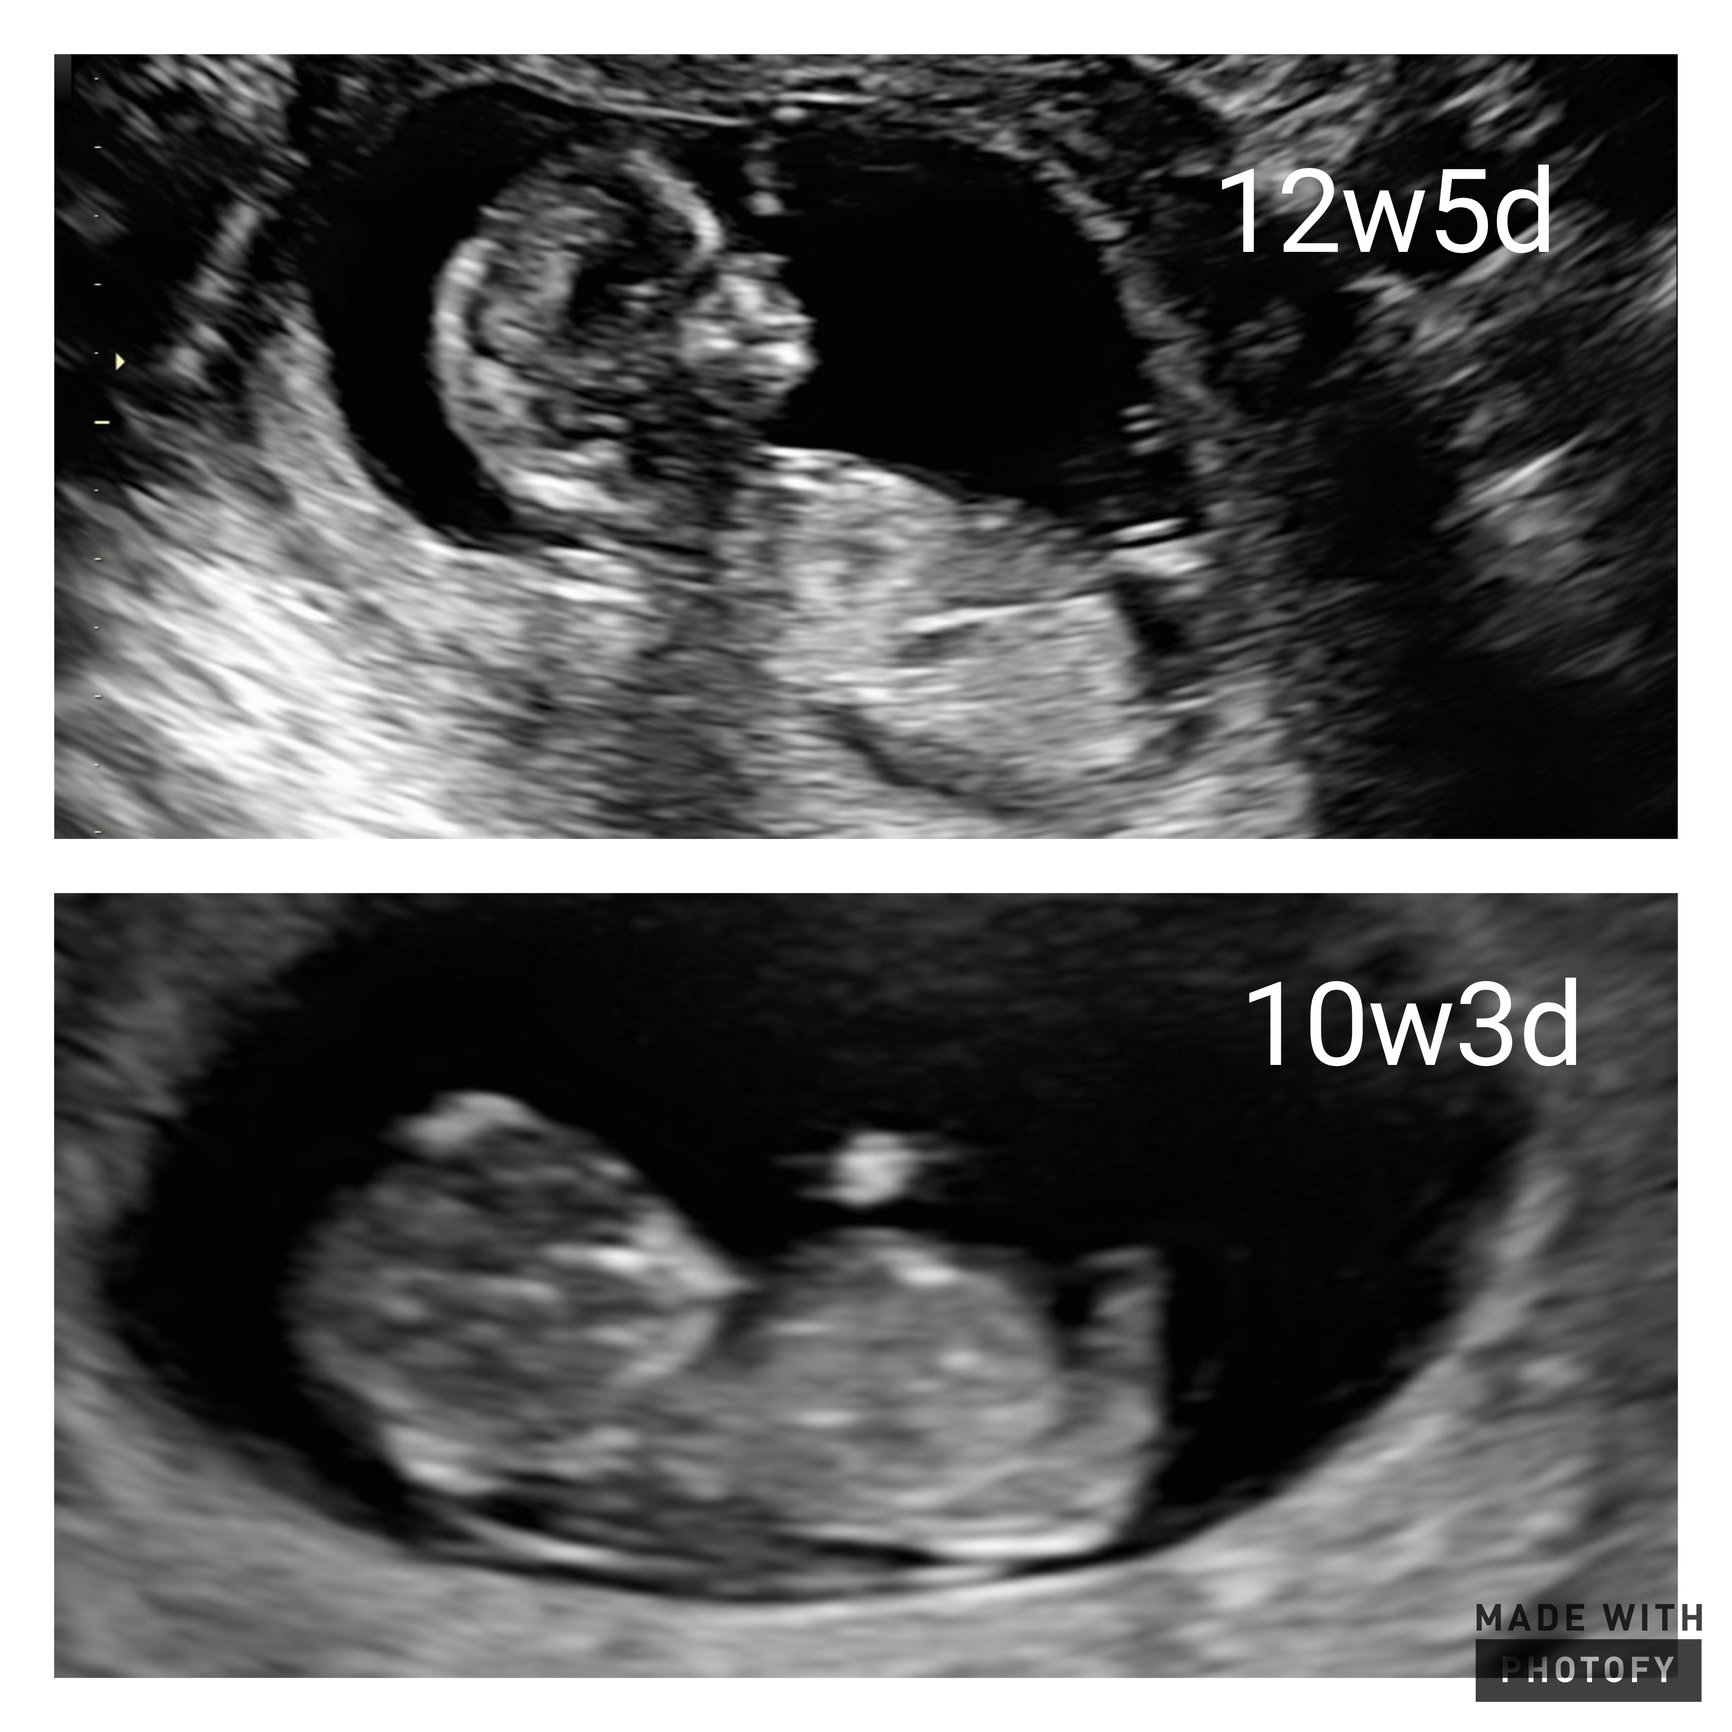

Crazy how much changes in 2 weeks!

Baby Girl Due: 1-1-22